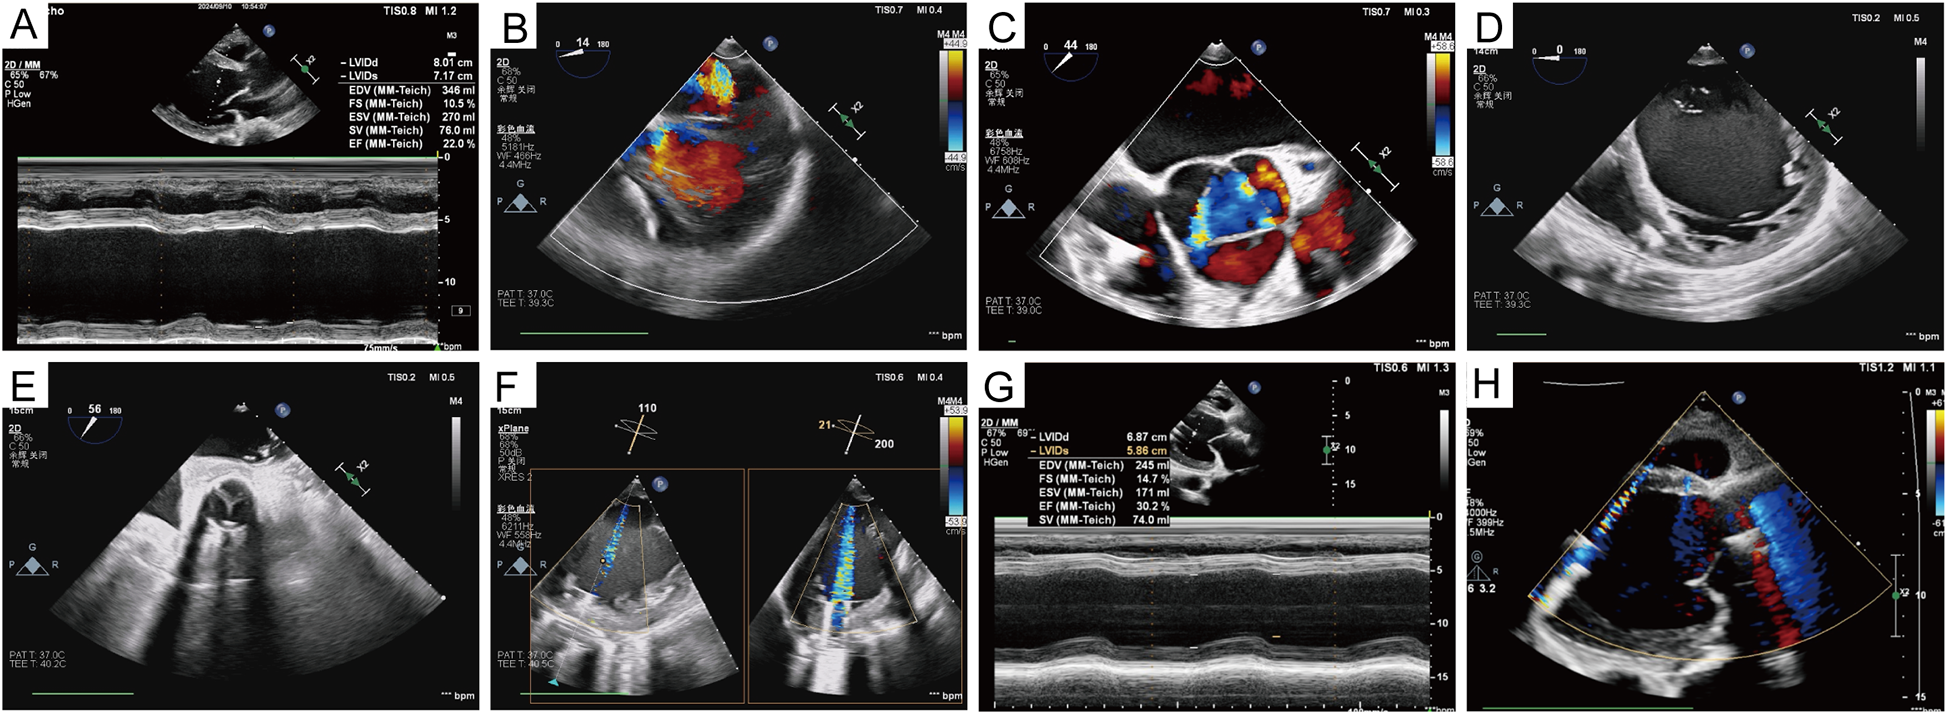

Figure 3

Echocardiographic data. (A) Preoperative ejection fraction and left ventricular diameter. (B–D) Mitral, aortic valve regurgitation, and left ventricular volume before left ventricular assist device implantation. (E) Opening and closing of the prosthetic valve. (F) The relationship between the inflow cannula of the left ventricular assist device and the mitral orifice and the ventricular septum was also demonstrated. (G,H) Left ventricular volume, as well as valve regurgitation, were significantly improved 1 year after the surgery.

Echocardiography after admission revealed dilated cardiomyopathy, severe aortic regurgitation, mild-to-moderate mitral regurgitation, moderate tricuspid regurgitation, reduced left ventricular systolic function, and general reduction in ventricular wall motion, with an ejection fraction of 22% and a left ventricular end diastolic diameter (LVEDD) of 80 mm. Coronary computed tomographic angiography (CTA) suggested the presence of varying degrees of mild stenosis in all coronary arteries, with no significant lesions identified (Figure 1B). Aortic CTA suggested an aortic root aneurysm, with a maximum aortic diameter of up to 53 mm (Figures 1C,D). Right heart catheterization showed a central venous pressure (CVP) of 3 mmHg, mean pulmonary artery pressure of 29 mmHg, and a total pulmonary resistance of 1.35 Wood units.

The patient exhibited oliguria on the first postoperative day (POD), accompanied by a rise in renal function index. The patient was placed on bedside continuous renal replacement therapy (CRRT). The patient's urine returned to a normal level on POD4. The patient was extubated on POD4. The patient had more pleural fluid postoperatively, which was deemed to be associated with exudate from the artificial vessel and the extensive surgical trauma. The drainage levels decreased, and the chest tube was subsequently removed on POD19. Heparin was administered, and the activated clotting time (ACT) was maintained at 160–200 s. The patient's warfarin was initiated on POD6, trying to maintain the international normalized ratio (INR) at 1.8–2.5. At 2 weeks postoperatively, the patient was able to ambulate and move without assistance. He was discharged on POD26 without any adverse events, while the LVAD achieved a pump flow of 3.08 L/min at 2,846 rpm. One year after the surgery, echocardiography revealed normal prosthesis function and reduced valve regurgitation, with an ejection fraction of 30% and an LVEDD of 68 mm (Figure 3). The chest x-ray taken 1 year after the patient was discharged from the hospital is shown in Figure 4.